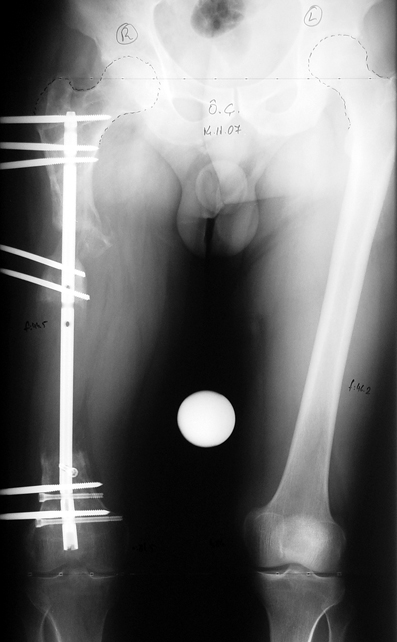

Appropriate radical debridement necessitates excision of all necrotic bone and soft tissues, and frequently causes instability at the involved extremity. The remaining bone and soft tissue defect has to be fixed and reconstructed. The distraction osteogenesis method of Ilizarov is used successfully for achievement of union, correction of the deformity, elimination of limb length inequality and reconstruction of segmental bone defects.

The duration of external fixation (external fixation index) depends on the amount of distraction required, and the extremity is prone to complications during this period. After the distraction phase is completed, the external fixator remains in place during the consolidation phase, which lasts twice as long as the distraction phase; but this period is hardly tolerated. If the external fixator is removed before sufficient consolidation is achieved, fractures, deformity and shortness will be the result. In our department, ‘lenghthening over nail’ method is used in order to decrease the external fixation index and increase patient comfort and activity level. In this method, the intramedullary nail is statically locked after the completion of the distraction phase, and external fixator is removed. The extremity is stabilized by the intramedullary nail during consolidation phase. In this way, complications due to long external fixation index or early removal of the external fixator are avoided.